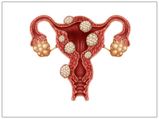

Uterus

Does Pregnancy Cause Uterine Fibroids?